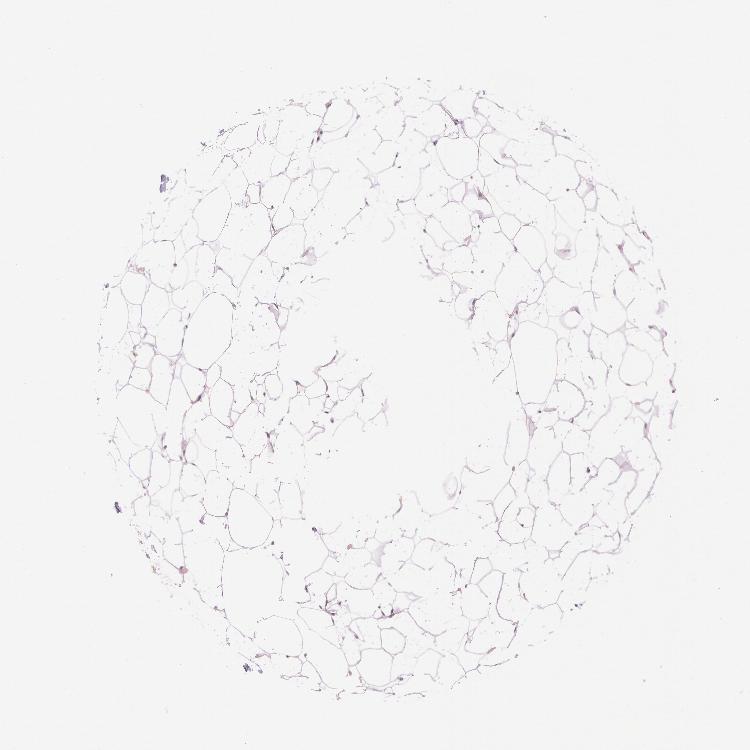

SOFT TISSUE 1 - Antibody stainingi

Antibody staining in the annotated cell types in the current human tissue is reported as not detected, low, medium, or high, based on conventional immunohistochemistry profiling in selected tissues. This score is based on the combination of the staining intensity and fraction of stained cells.

Each image is clickable and will lead to virtual microscopy that enables deeper exploration of all samples and also displays staining intensity scores, fraction scores and subcellular localization as well as patient and tissue information for each sample.

Antibody HPA001427Antibody HPA019665

Fibroblasts Not detectedLow

Peripheral nerve -Low